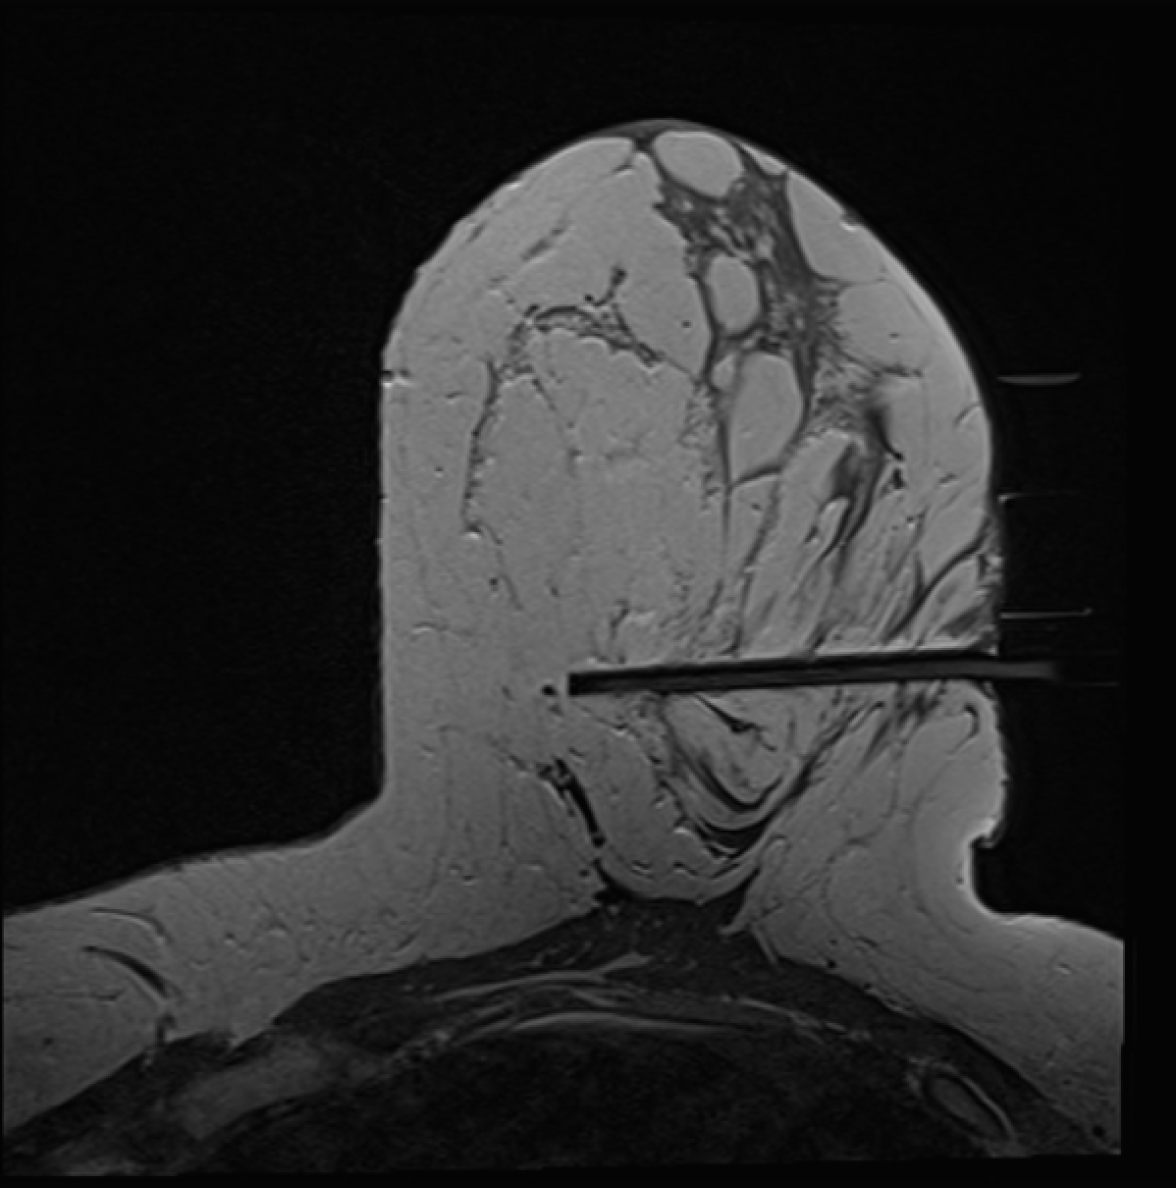

Une macrobiopsie mammaire peut être guidée par mammographie, échographie ou IRM et dure entre 20 et 40 minutes. La salle d’examen varie donc en fonction du mode de guidage indiqué.

En salle d’examen, vous prendrez place en position allongée sur le dos ou sur le ventre selon la technique utilisée par le radiologue. Après l’administration d’une anesthésie locale, le radiologue interventionnel effectue le ou les prélèvements qui seront par la suite transmis au laboratoire pour analyse.

Au cours d’une macrobiopsie mammaire, l’aiguille utilisée est de calibre plus important (5 à 10 mm), ce qui permet le prélèvement d’échantillons plus volumineux (10 à 30 fois supérieur) et de réaliser les prélèvements requis en une unique ponction.